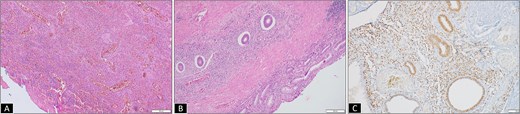

(A) Micrograph from initial rectal polyp biopsy showing complete mucosal ulceration with underlying inflammatory granulation tissue (H&E 100×). (B) Micrograph from resection specimen showing colonic mucosa with ectopic endometrial glands and stroma traversing transmurally from the lamina propria to muscularis propria (H&E 200×). (C) Endometrial glands and stroma highlighted by estrogen receptor (ER, IHC 200×).

A 37-year-old female presented with a 2-year history of non-cyclical, recurrent rectal bleeding, significant weight loss, altered bowel habits, and spontaneous passage of polypoid tissue per rectum. Advanced imaging modalities, including computed tomography scan and contrast-enhanced MRI, demonstrated an aggressive local disease pattern with transmural rectal wall thickening, mesorectal fat stranding, and loss of intervening fat planes, features favoring a malignant lesion (Fig. 1A and B). Despite extensive diagnostic workup, including multiple biopsies, findings remained inconclusive, limited to nonspecific granulation tissue, inflammatory changes, and hyperplastic or adenomatous polyps with low-grade dysplasia. Pelvic imaging also revealed uterine fibroids and adnexal abnormalities. Ongoing diagnostic uncertainty necessitated a lower anterior resection with diversion loop ileostomy, which was complicated by persistent postoperative purulent discharge and poor clinical recovery, Gross examination of the resected rectal segment showed a diffusely thickened wall with multiple mucosal ulcerations and a well-circumscribed polypoid lesion measuring 3 cm in maximum dimension (Fig. 1C). Histological evaluation revealed ulceration with granulation tissue, along with multiple foci of ectopic endometrial glands and stroma within the submucosa and muscularis propria. Immunohistochemistry (IHC) confirmed the endometrial origin, with strong estrogen receptor (ER) positivity in both the glands and stromal component (Fig. 2). These findings confirmed the rare diagnosis of polypoidal rectal endometriosis, illustrating the protean clinical and pathological manifestations of the disease and its potential to mimic malignancy, leading to significant diagnostic delay.